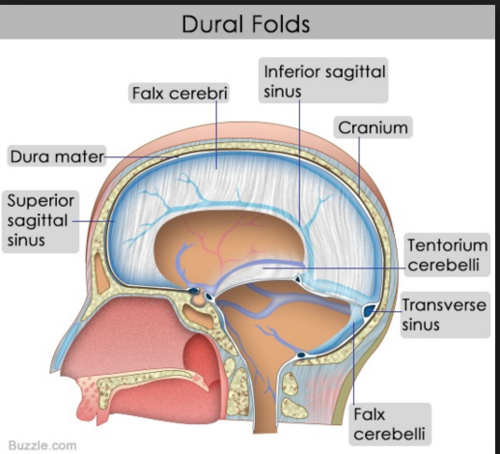

Cranial Dural Folds

Falx cerebri

Tentorium cerebelli

Falx cerebelli.